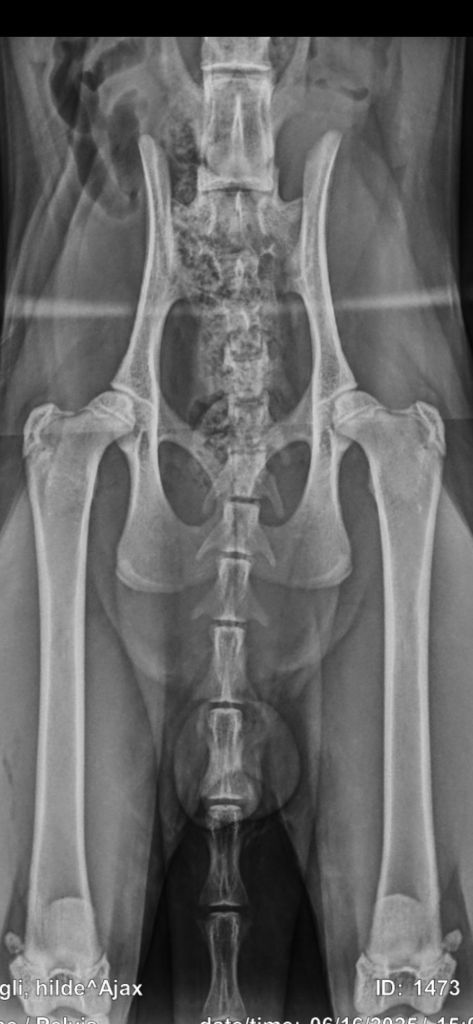

Røntgen av hofter på Ajax

I og med at Ajax går i sammen med jentene her hjemme valgte jeg å ta røntgenbilder av hoftene hans litt tidlig for å få en viss formening om at det ikke ser håpløst ut. Jeg er ikke utdannet på noe måte, men har sett mange bilder før. Dette er hofter som ikke skremmer meg så mye fra å lan han fremdeles får gå fritt med jenten Disse bildene er tatt når Ajax var 8 mnd. 😉